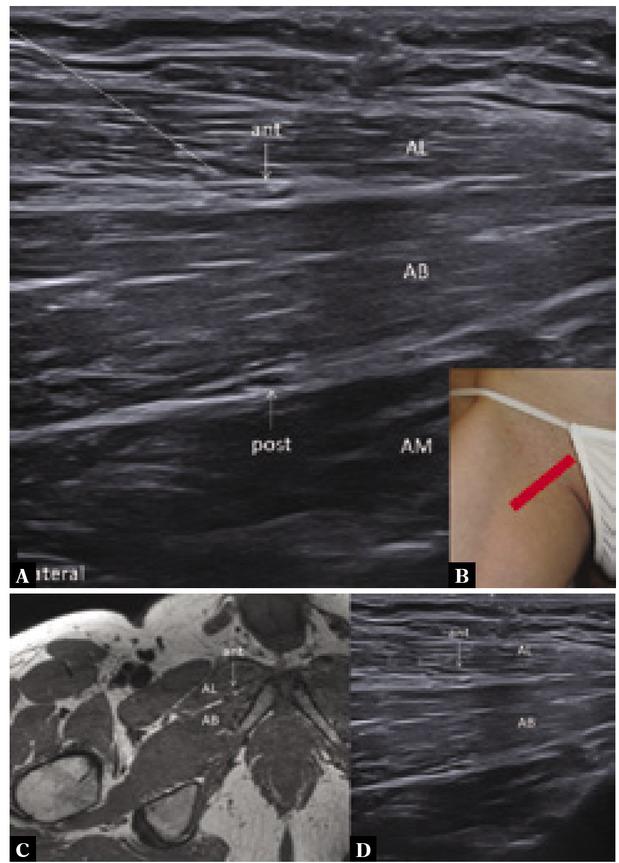

Fig. 3